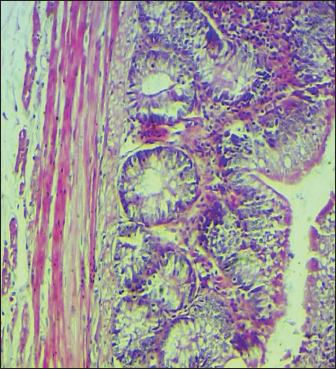

Histopathological study

The results noted in Figures 15 showed that chicks infected with S. enteritidis had edema among the muscular layer with atrophy of some intestinal villi. On the other hand, broilers infected with S. enteritidis and treated with C. myxa showed degeneration of intestinal glands with extensive inflammatory cell infiltration also mild sub-muscular edema, while with curcumin-treated group showed normal intestinal villi architectures, with hyperplasia of intestinal associated lymphoid tissue. The result noted a clear improvement in broilers that received C. myxa and curcumin showing normal intestinal villi with an increase in the number of goblet cells. The data of the present study confirmed the effectiveness of C. myxa and curcumin and especially the synergistic action between them in inhibiting the growth of S. enteritidis bacteria in poultry chickens, improving antioxidants and reducing free radicals, in addition to its action as a good anti-inflammatory at the blood level and suppressing the levels of cytokines that encourage inflammation and its role in improving intestinal tissues and making them close or similar to the health of broiler.

Fig. 5. Cross section of the intestine of poultry chicks infected with S. enteritidis and treated with C. myxa and curcumin showing normal intestinal villi with an increase in the numbers of the goblet cells (H&E stains, 100×).